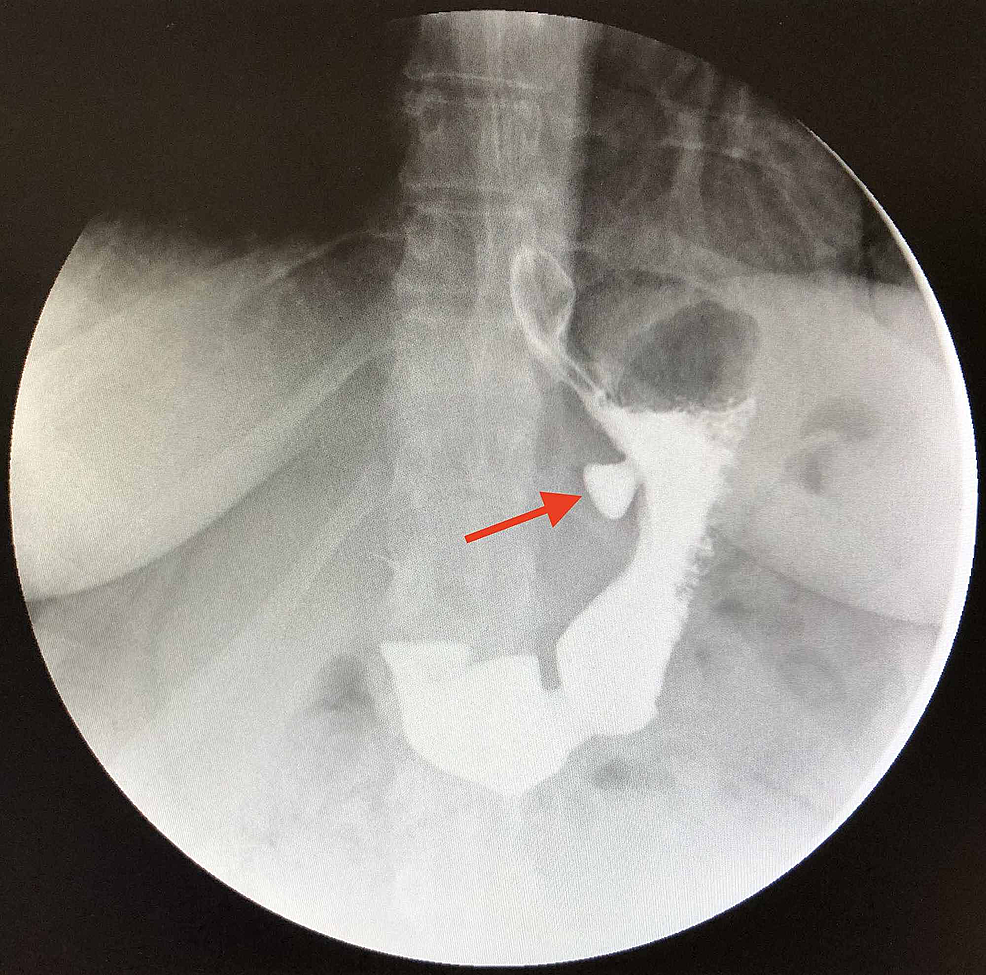

Epidemiology gastric diverticula are rare and c. Weight loss surgery is about reducing your weight and gaining good health. Gastric diverticula are sac like projections that usually originate from the gastric fundus most commonly on the posterior surface. They are the least common of the gastrointestinal diverticula.

Cain jc jordan gl jr comfort mw gray hk. J am med assoc. The gas tric fundus is dened as the portion of the stomach craniad to the gastric car dia. Commonly accompanying this are abnormally dilated short gastric veins which pass from the splenic vein to encircle the gastric fundus and form gastric fundal varices.